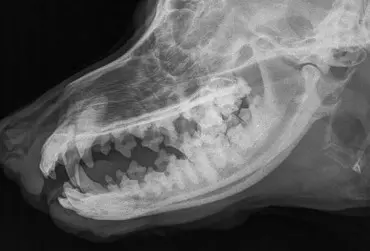

Choroby ślinianek są rzadkie u psów. Najczęściej występującą nieprawidłowością jest mucocele. Do przyczyn tego zaburzenia można zaliczyć urazy, ciała obce lub kamienie ślinowe, dirofilariozę, nowotwory oraz przyczyny idiopatyczne. Do zaburzenia dochodzi również po zabiegach mandibulektomii. W artykule opisano przypadek psa z mineralizacją w okolicy odpowiadającej umiejscowieniu przewodu ślinianki przyusznej.